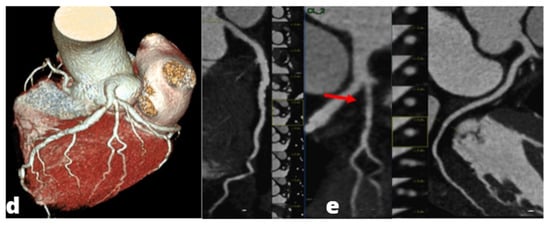

Figure 5.

Acute Coronary Syndrome. A patient presenting to the emergency department with acute chest pain. No significant cardiac enzyme elevation and ECG alteration. Cardiac CTA shows absence of significant stenoses in the right coronary artery (a) and the left circumflex (b); a significant stenosis in the proximal anterior descending artery (c) is present, confirmed by subsequent coronary angiogram (d).